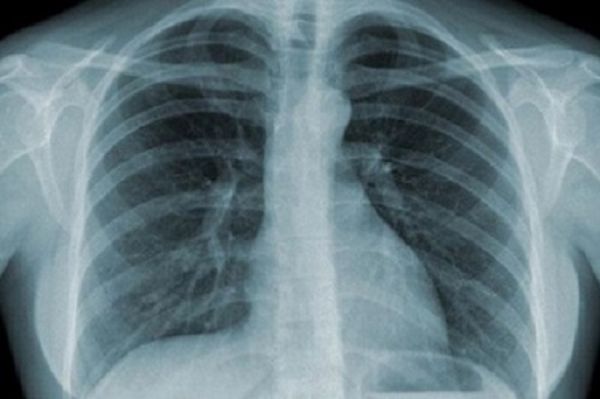

Ung thư phổi thể trung tâm

Đại đa số các khối u ung thư phổi. Phổ biến nhất, nó phát sinh từ các pseudo-phân tầng biểu mô niêm mạc của đường hô hấp phế quản nhưng cũng có thể phát sinh từ các biểu mô cuối đường hô hấp nhỏ và phế nang. Trên thế giới, ung thư phổi là nguyên nhân phổ biến nhất gây tử vong liên quan ung thư.